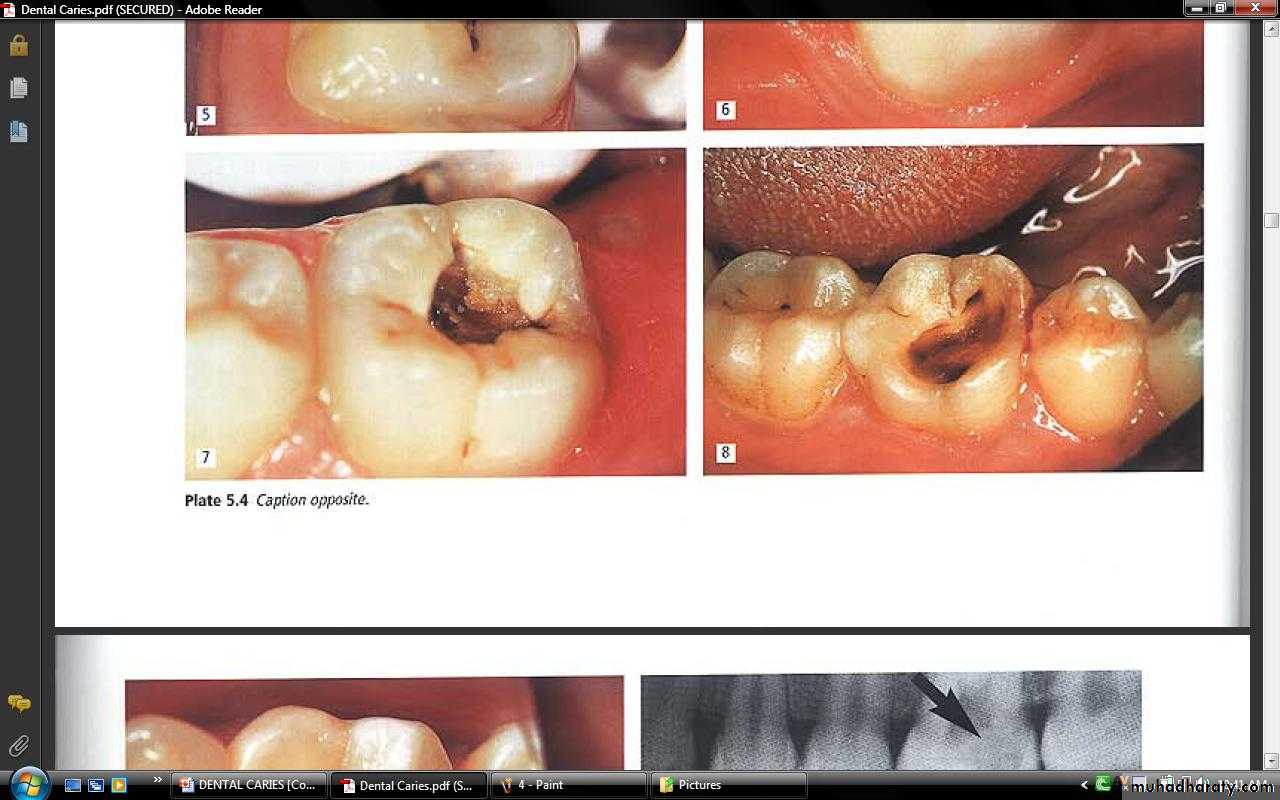

ACUTE DENTAL CARIES

It is that form of caries that follows a rapid clinical course and results in early pulpal involvement by carious process.Predominantly affects children and young adults probably because their dentinal tubules are larger and show no sclerosis.

The point of entry of caries is small even though there is rapid spread of caries at DEJ, producing large internal cavitation.

The small point of opening doesn’t allow the buffering ions of saliva to neutralize acids formed within the cavity.

The affected dentin is usually stained light yellow compared to deep brown / black of chronic caries.

CHRONIC DENTAL CARIES

That type of caries which progresses slowly and involves the pulp much later than acute caries.Most commonly seen in adults.

Opening to the lesion is invariably larger than that of acute caries. As a result, there is lesser food impaction and greater access to saliva.Also, the slow progress of caries allows enough time for dentinal sclerosis and deposition of tertiary dentin in response to irritation.

The carious dentin is stained deep brown

As compared to acute caries there is considerable SURFACE destruction with a shallower cavity and little undermining of there is only enamel, while moderate spread of caries along the DEJ.Pain is NOT a prominent feature here due to the protection provided to the pulp by tertiary dentin formation.